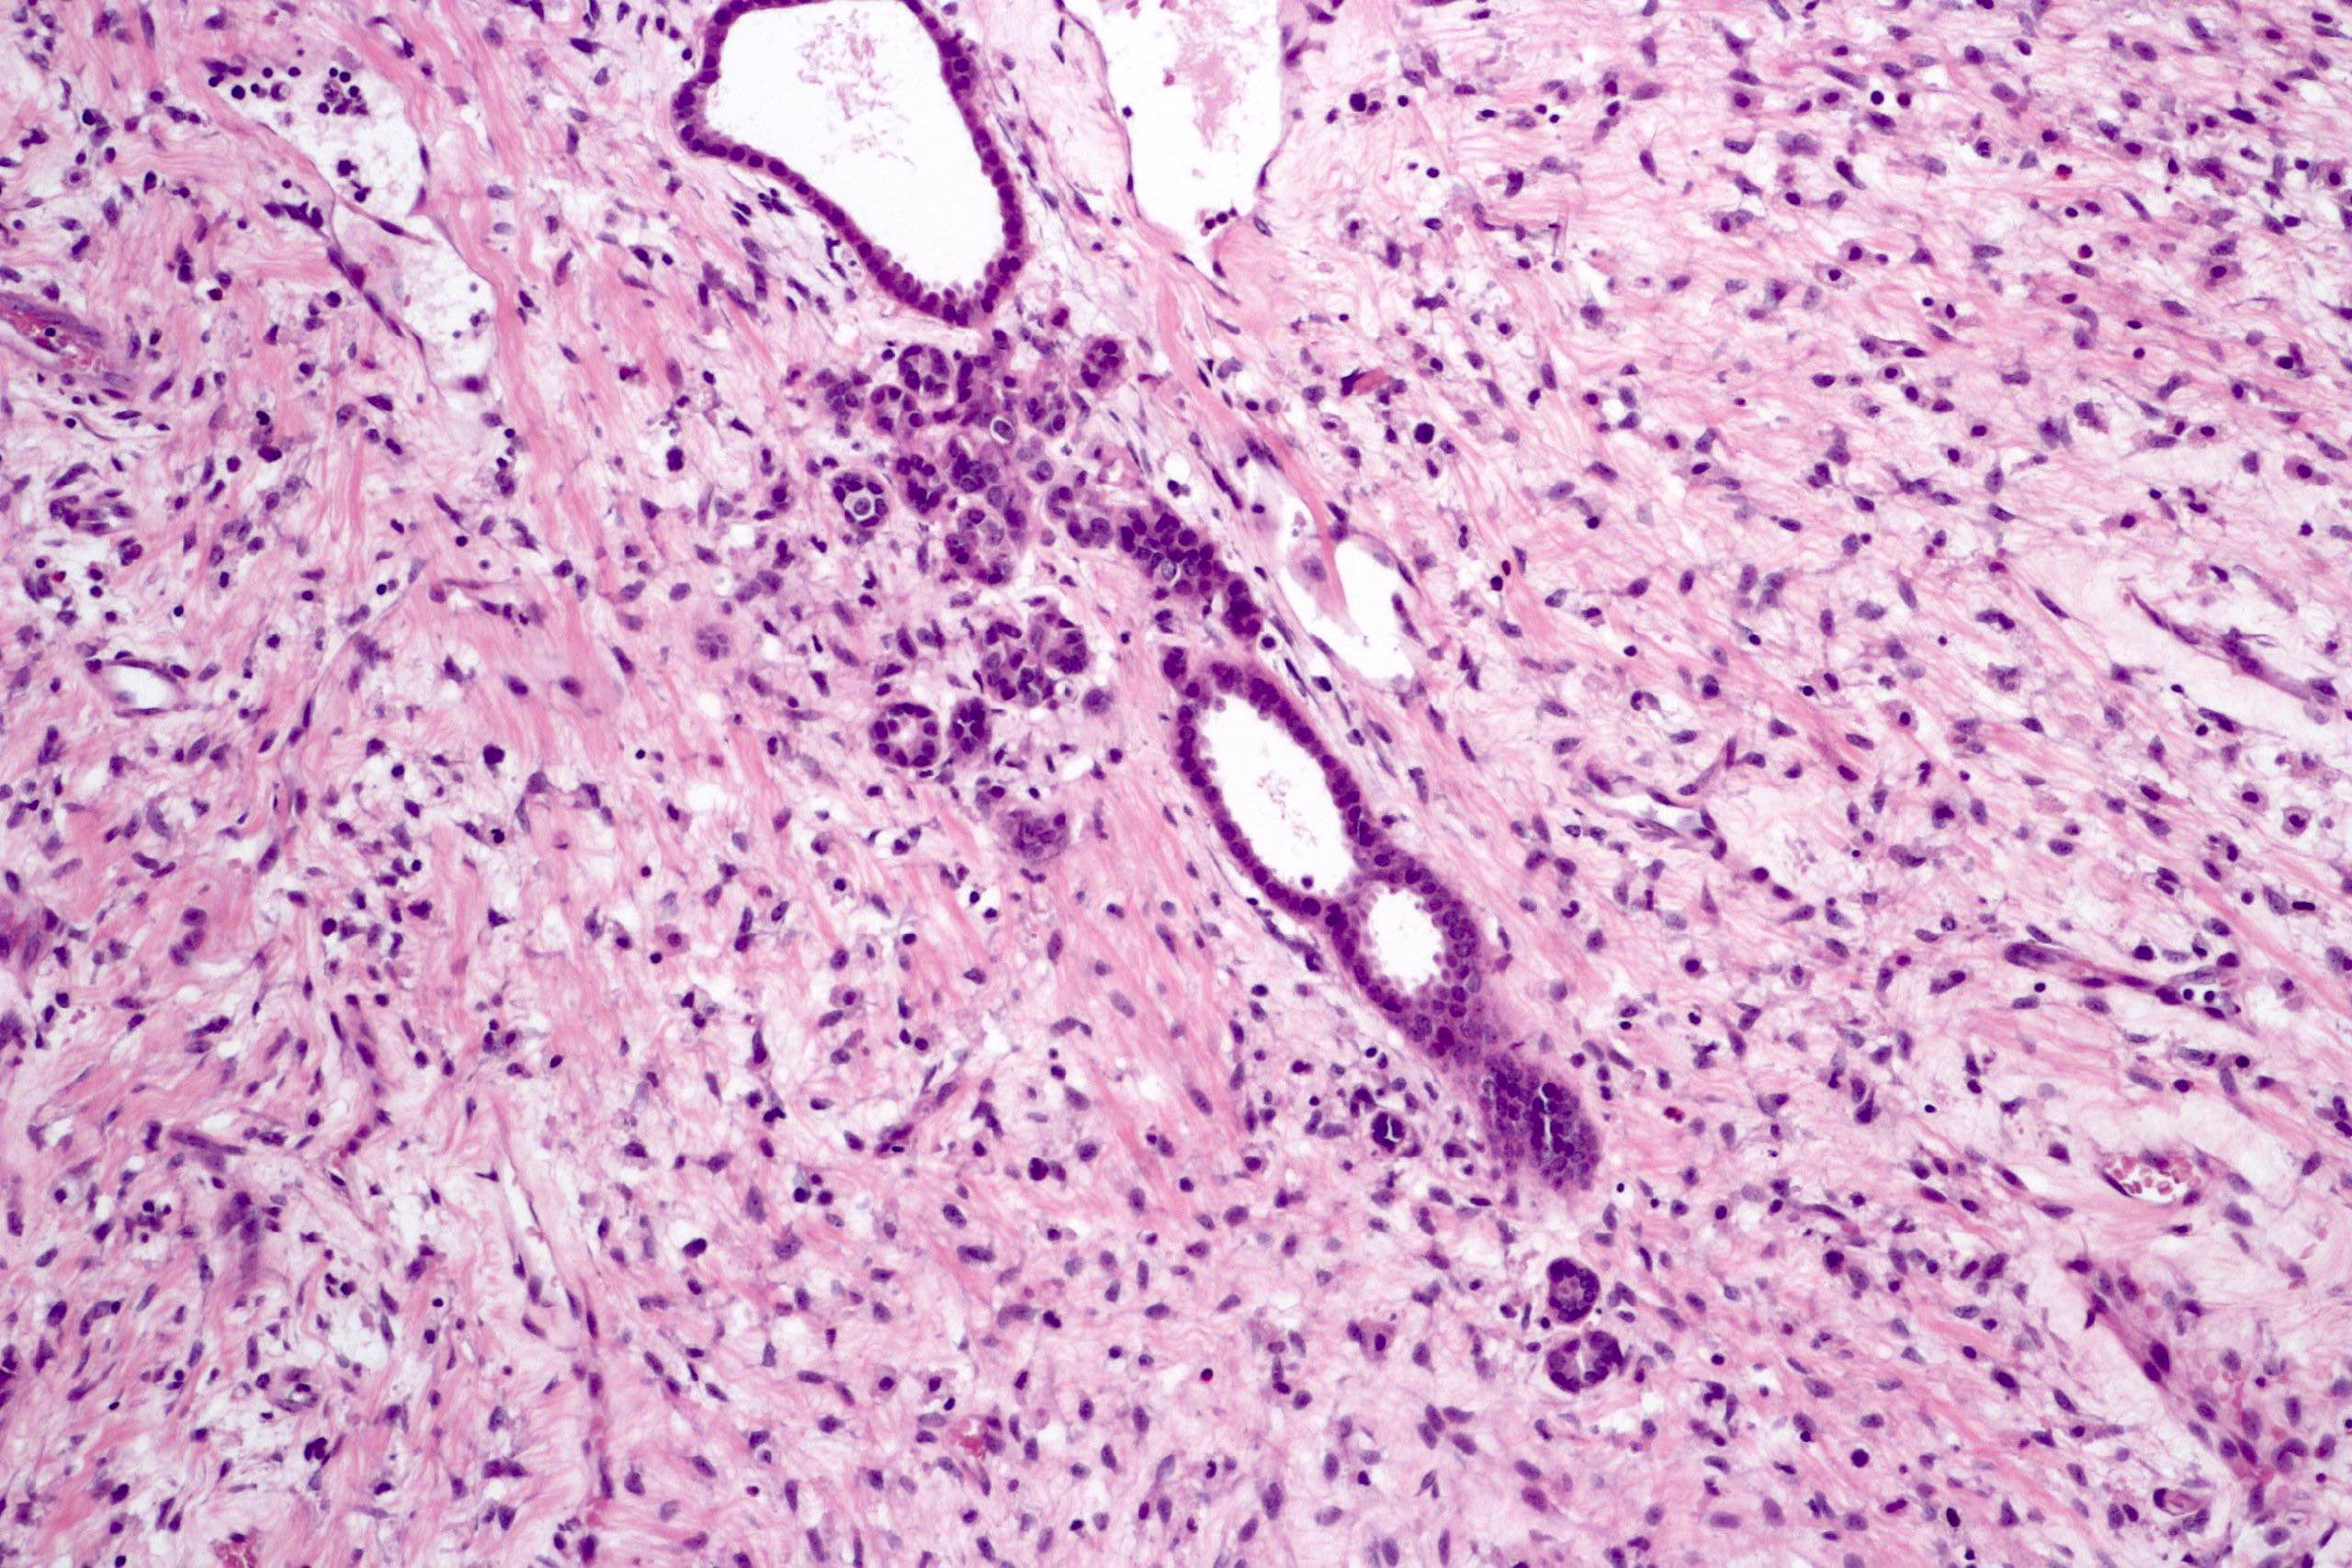

Microscopic (histologic) description

- Cysts lined with flat / cuboidal / hobnail cells (or are denuded)

- Epithelial elements consist mainly of mature and immature / abortive tubules and small papillae resembling immature glomeruli

- Key histological findings of the variably cellular septa include

- Nephroblastomatous epithelial elements

- Islands of undifferentiated blastema and differentiated mesenchymal elements (skeletal muscle and less often cartilage and fat) (J Urol 2010;183:1585)

- Focally, the septal elements may protrude into the cystic spaces in microscopic papillary folds

Microscopic (histologic) images

Contributed by Americo Brilhante, M.D. and Daniel Athanazio, M.D., Ph.D.